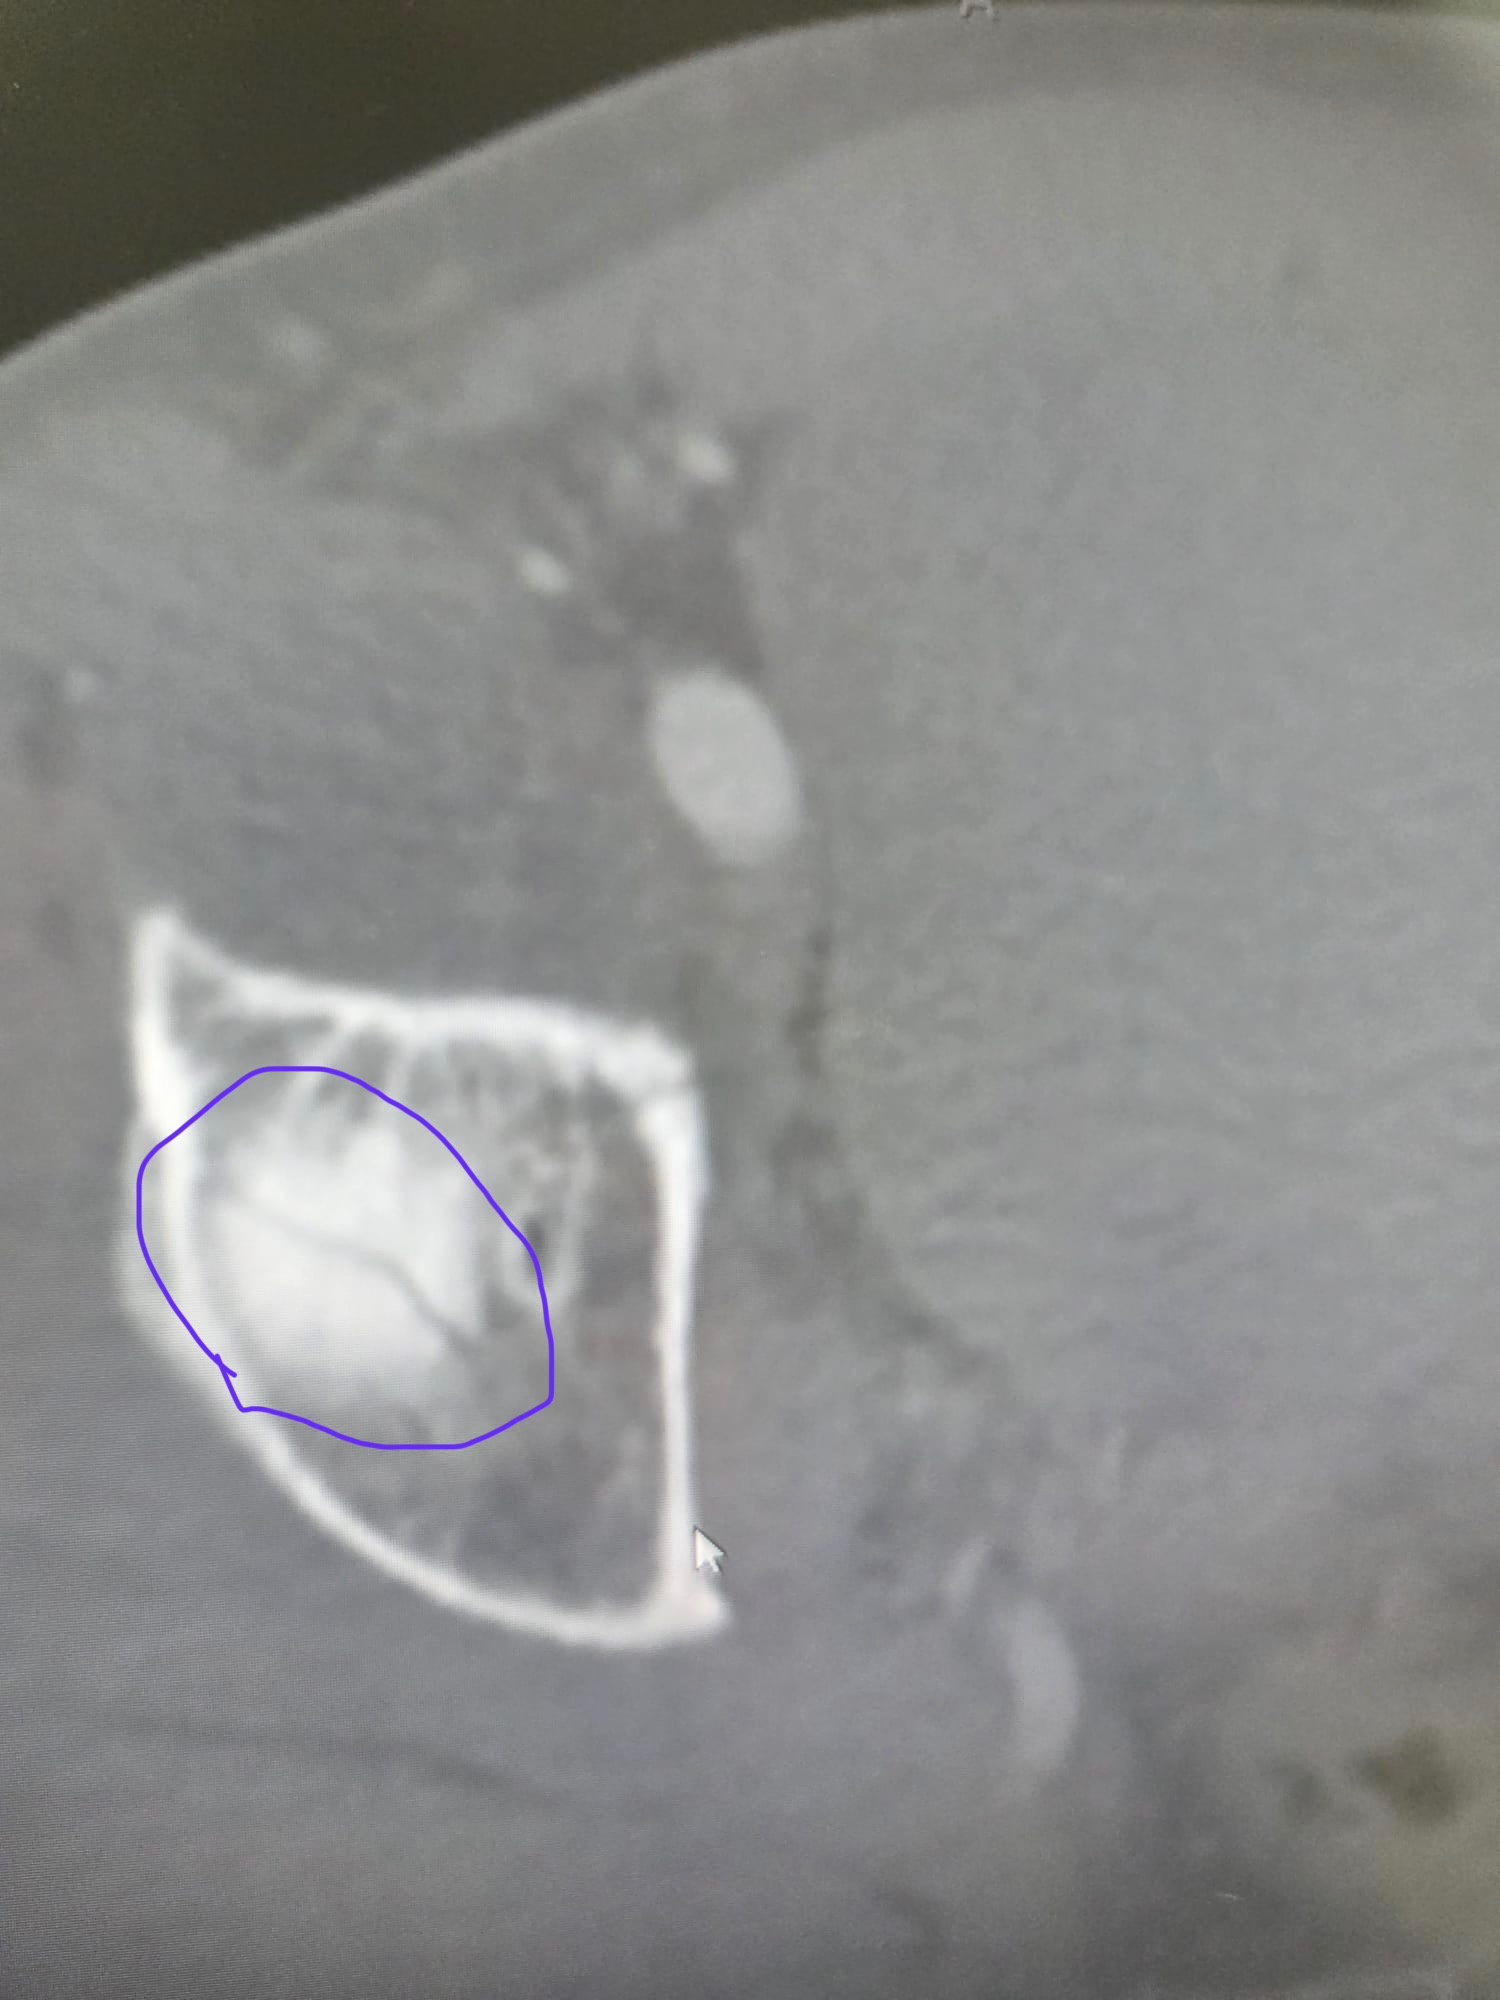

On March 14th, local friend and avid cyclist Luis Pagan was finishing his usual Saturday endurance training ride in Key Biscayne. After coming down the Rickenbacker Bridge, he accidentally hit something on the bike lane and unfortunately lost control of the handlebar, causing him to fall off the bike at high speed. Other cyclists in the area noticed he was hurt and offered immediate assistance. Paramedics arrived shortly after and transferred him to the ER at Jackson Memorial Hospital. Luis was seen by multiple doctors and specialists, including an orthopedic surgeon and trauma team, who confirmed he has a fractured hip, dislocated shoulder, sprained wrist, and multiple skin burn lacerations.

Luckily, Luis did not suffer any head injuries. However, CT scans show that he will need further examination (MRI) and treatment for his injured shoulder and fractured hip. After being discharged from the hospital, he has been instructed not to put any weight on his right leg for at least six weeks and then it will require several weeks of physical therapy . Please support Luis' recovery journey with any donations so that he can get a speedy recovery and back on his feet. The funds raised will go toward medical bills, living expenses, and therapeutic items to support his recovery.